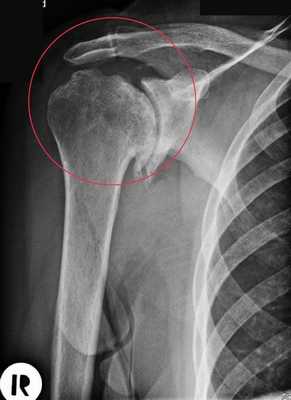

Артроз плечевого сустава на рентгене.

В зависимости от степени повреждения выделяют следующие виды эндопротезирования плеча:

- Однополюсное. Производится имплантация либо лопаточной впадины, либо костной головки.

- Полное. При этом меняются все соприкасающиеся части: и головка, и впадина. Причем возможны два варианта замены: имплантируются только суставные элементы или производится установка протезов на стержне с креплением в костной полости.